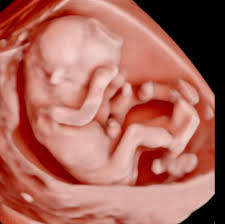

A Ultrassonografia Obstétrica Inicial é essencial para confirmar a gestação, avaliar a localização do saco gestacional e estimar a idade gestacional com precisão. Além disso, permite verificar a presença do batimento cardíaco fetal e identificar gestações gemelares precocemente. Esse exame é fundamental para garantir um acompanhamento seguro e adequado desde o início da gravidez, além de ser o primeiro momento de conexão entre mãe e bebê.

A Ultrassonografia Morfológica do 1º Trimestre é um exame fundamental para avaliar o desenvolvimento inicial do bebê. Realizado entre 11 e 14 semanas, ele permite:

✅ Avaliar os marcadores cromossômicos, entre eles, translucência nucal, osso nasal, ducto venoso e fluxo tricúspide, auxiliando na triagem de síndromes genéticas, como a Síndrome de Down.

✅ Verificar a formação inicial dos órgãos e estruturas fetais.

✅ Avaliar o risco de pré-eclâmpsia e outras complicações da gestação.

Esse exame é um dos primeiros passos para um acompanhamento seguro e detalhado da gestação,

Considerado por muitos o principal exame da gestação!